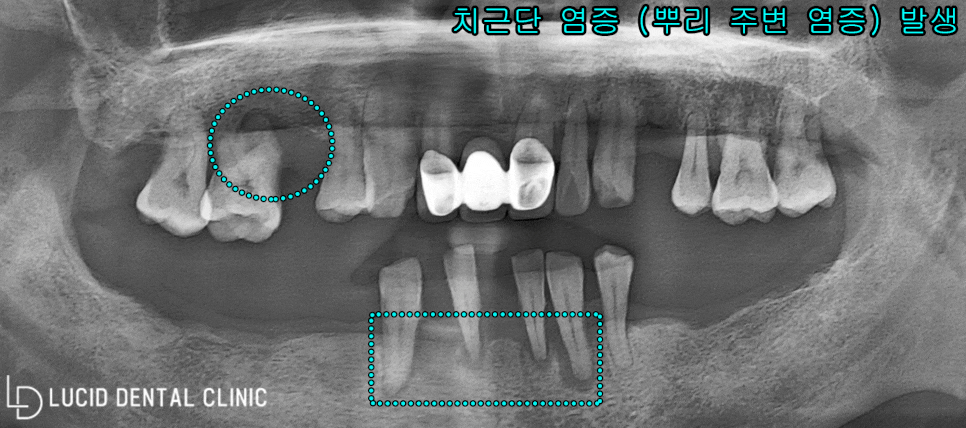

- 검진 결과 및 진단

<파노라마 엑스레이의 경우,

본래 환자의 구강과 반대로 나오니

사진을 기준으로 설명하겠습니다.>

진단 결과, 현재 환자 구강 속에

치근단 염증(뿌리 주변)

심한 치조골 퇴행(내려감)

이미 발치하여 빈 어금니

총 3가지의 문제를 발견할 수 있었습니다.

잔존치 역시 정출이 시작되며 보존이 어려웠고

잔존 치조골의 양 또한 현저히 적어 보였습니다.

만약, 임플란트 수술 을 진행한다 하면

보다 단단히 픽스처를 고정할 수 있도록

꽤 많은 양의 골 이식 과정이 필요할 겁니다.